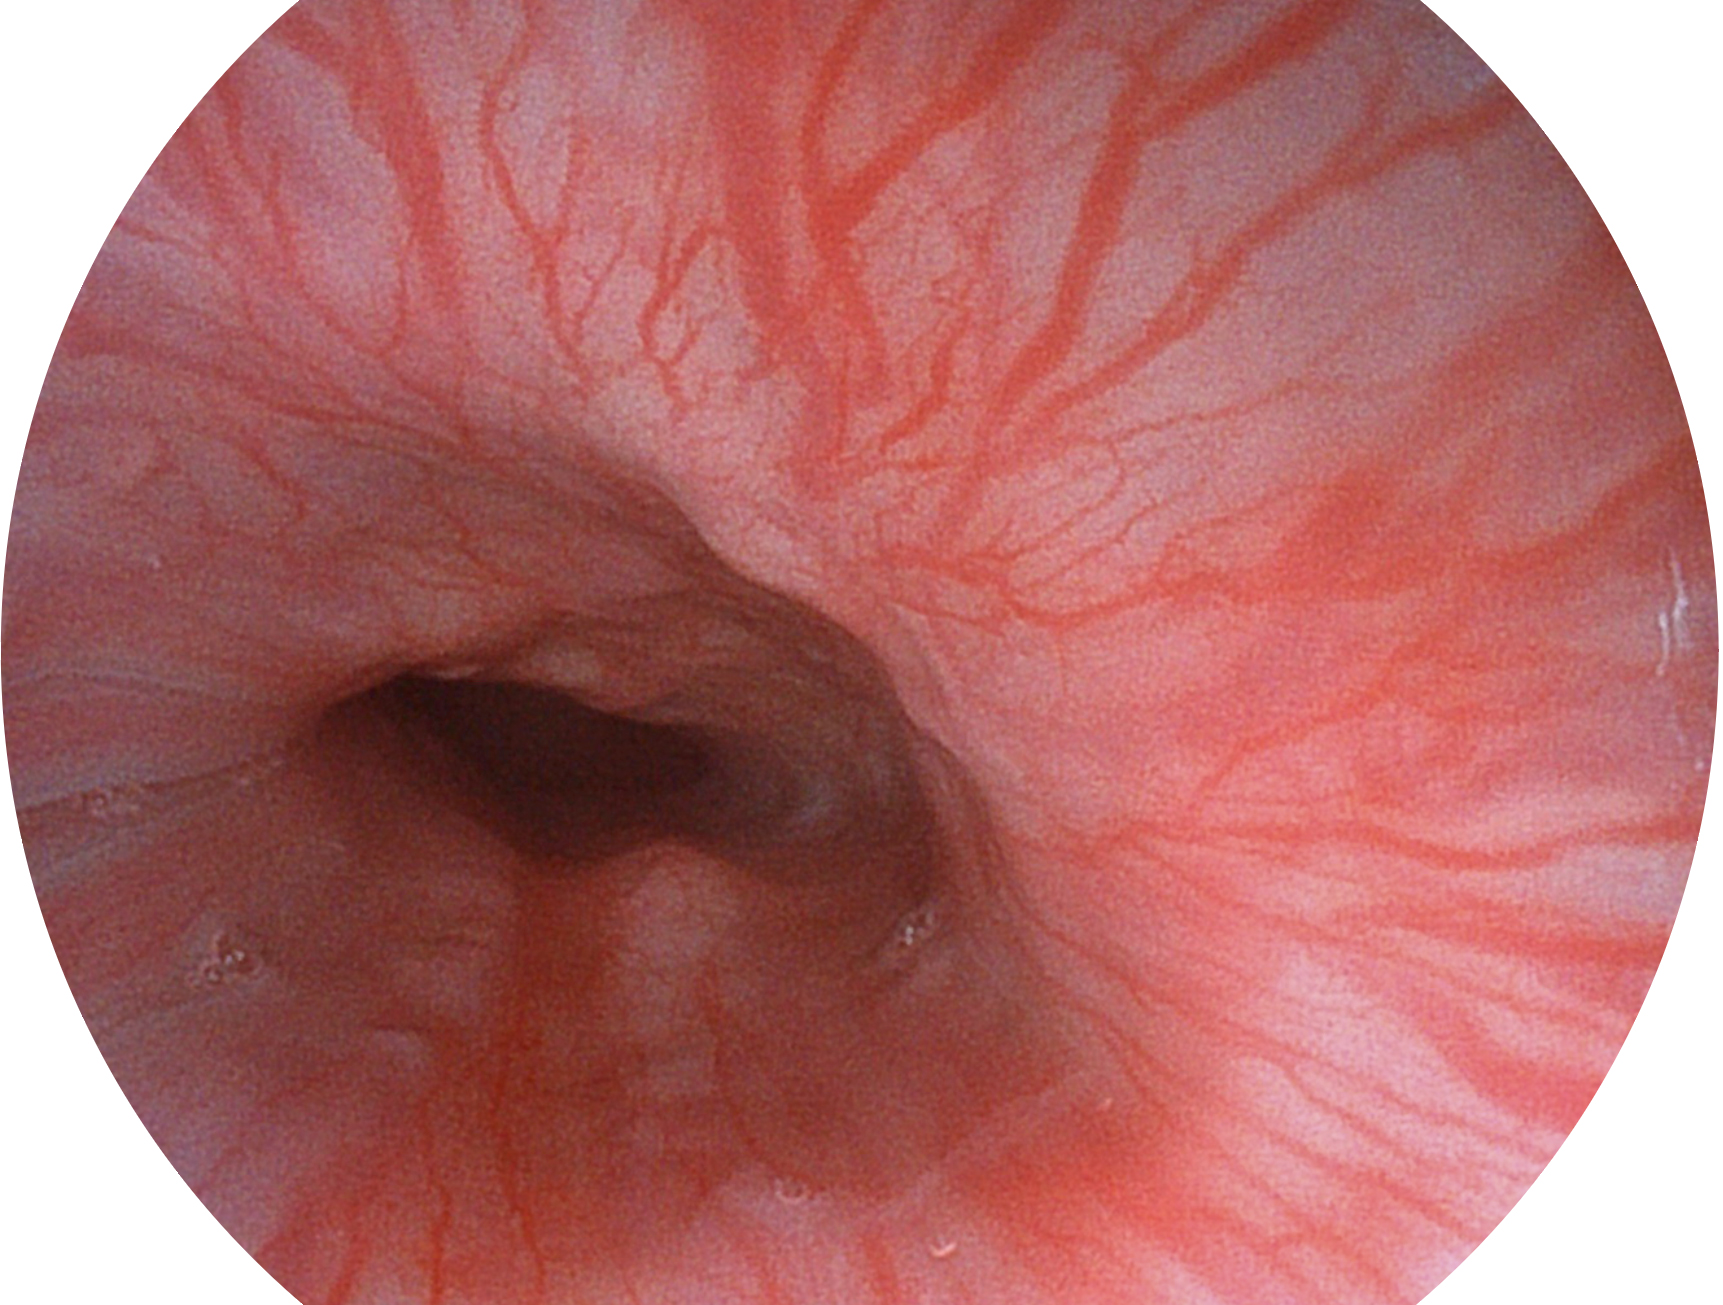

银河优越会新开发的内镜染色技术,主要是基于多波长LED 光源的开发,VLS-55Q 四波长LED 光源是由四个不同颜色的LED光按照相应照明模式所规定的特定发光比例进行合束后形成,合束后形成的照明光的光谱由红光、绿光、蓝光及蓝紫光这四个不同的波段范围构成。具有更高光谱自由度,通过光谱比例的控制,实现了聚谱成像技术,英文全称为“Spectral Focused Imaging, SFI”,缩写为“SFI”和光电复合染色成像技术,英文全称为“Versatile Intelligent Staining Technology, VIST”,缩写为“VIST”。